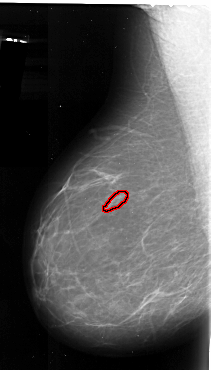

A_1083_1.LEFT_MLO

LEFT_MLO LINES 6286 PIXELS_PER_LINE 3571 BITS_PER_PIXEL 16 RESOLUTION 42 OVERLAY

FILE: A_1083_1.LEFT_MLO.OVERLAY

TOTAL_ABNORMALITIES 1

ABNORMALITY 1

LESION_TYPE CALCIFICATION TYPE PLEOMORPHIC DISTRIBUTION LINEAR

ASSESSMENT 4

SUBTLETY 2

PATHOLOGY MALIGNANT

TOTAL_OUTLINES 1

BOUNDARY